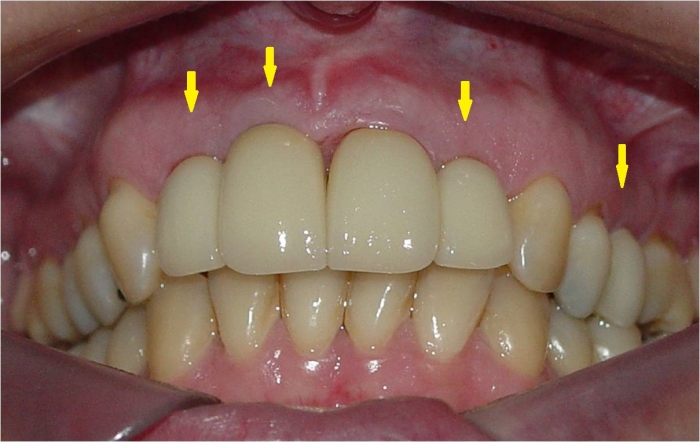

Dentes individuais em porcelana

Sorriso final, do caso terminado em abril de 2013